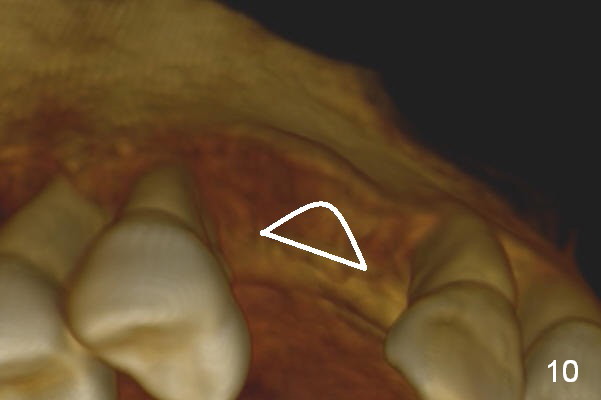

Retrospectively, bone expansion should have been initiated (Fig.9 white line) close to the thicker palatal plate (P). The coronal end of the osteotomes should have been directed palatally. It would be much better to use a D implant (Fig.10).